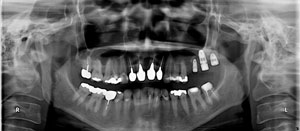

M.K‚³‚ñ @55Î —«@@@Ž©‰c‹Æ@Žèp“ú@‚Q‚O‚O‚U”N ‚WŒŽ ‚W“úi‰Îj  Ã–¬“à’ÁÖ@•¹—p@@

@@     @@@ãŠ{ ‚R–{  ‘¦Žž‰×d@  #‚P‚V #‚P‚U #‚P‚S•” @@

@@@@@@@@@@@@@ƒTƒCƒiƒXƒŠƒtƒgiƒ‰ƒeƒ‰ƒ‹j{ƒCƒ“ƒvƒ‰ƒ“ƒg‚R–{–„“ü@@